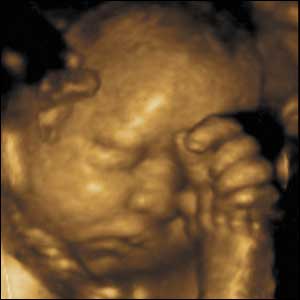

34 weeks gestation. 34cm from crown to rump.

8 of 10

While newborns do not smile until 4-6 weeks after birth, babies in the uterus do. Maybe because the uterus is warm, comfortable, and shielded from loud noise and bright light.